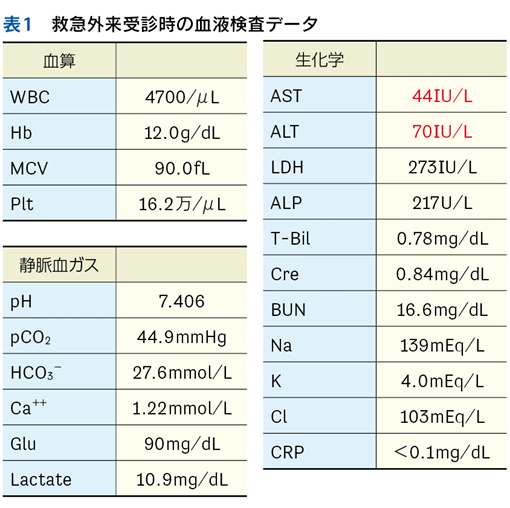

▶ semanticは直訳すれば「意味の」となるが,semantic qualifierを診断推論の文脈で訳すなら,「意味を限定する修飾語句」とでもなるだろう。先述のように,フレーミングに用いる問題を定義するにあたっては,個別具体的な情報は捨象され,抽象化・一般化された概念となっている必要がある。ゆえにSQも抽象的・一般的な医学用語に「翻訳」して表現する(表1)。